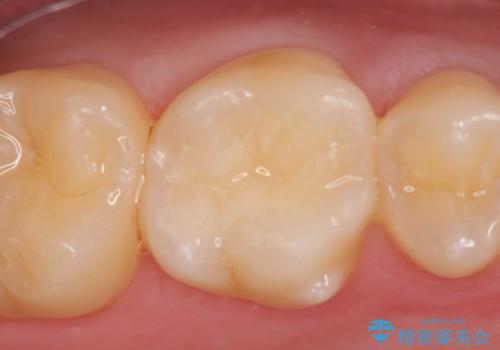

検診による初期虫歯の早期発見・早期治療

- 7万円 (emaxインレー)費用は治療当時の料金となります

症状は特にありませんでしたが、検診で全体をチェックすることで虫歯を小さなうちに早期発見し治療することができました。